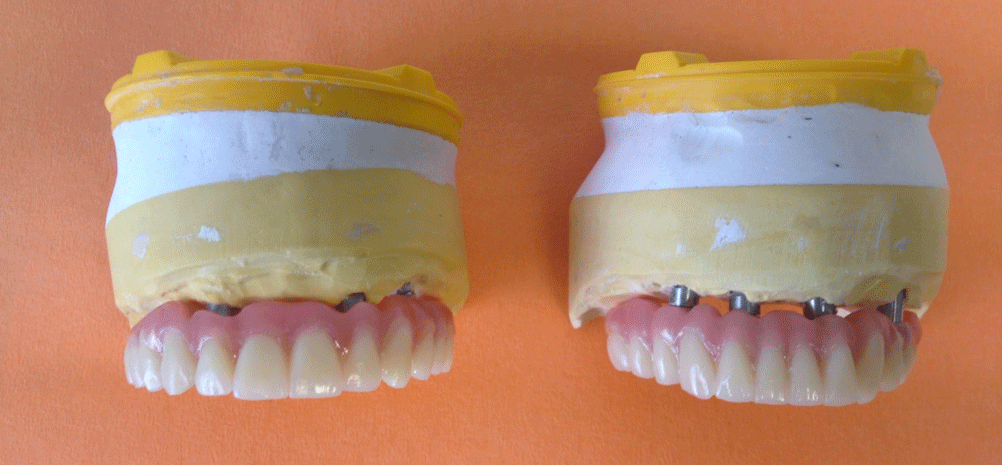

Intervento e consegna Protesi Definitiva Fissa – Tutto nella stessa seduta –

In un’unica seduta al paziente sono stati posizionati quattro impianti (tecnica All On Four) e inserita la nuova protesi fissa definitiva, avvitata sui nuovi quattro impianti.